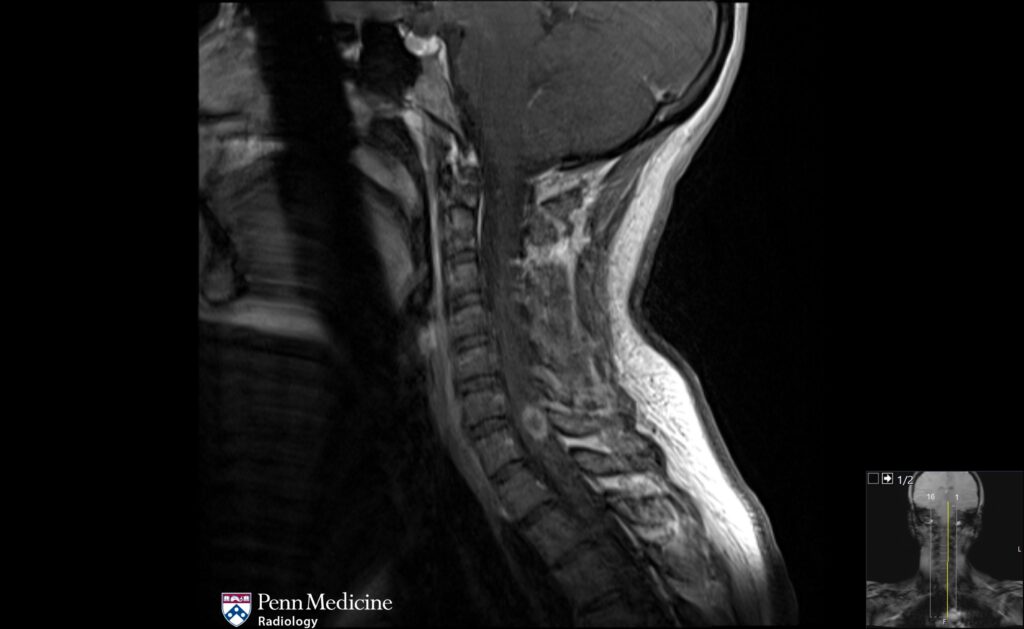

30-year-old woman with numbness of the torso

A 30-year-old woman with several days of sudden-onset numbness to her torso.